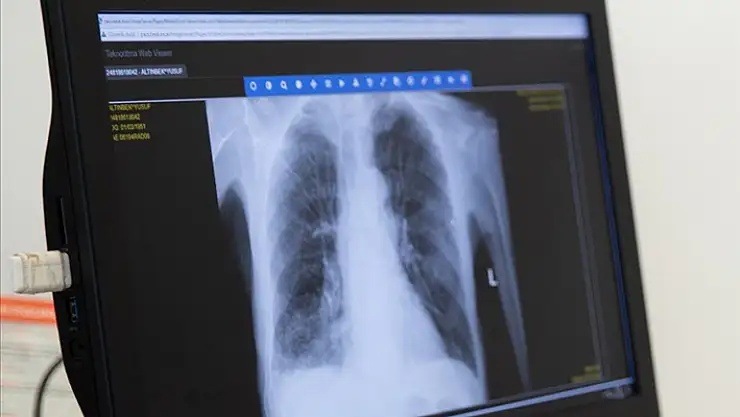

Ankara Şehir Hastanesi Göğüs Hastalıkları Kliniği Eğitim Görevlisi Prof. Dr. Hatice Kılıç, KOAH'ın genellikle öksürük ve balgam çıkarılması, nefes darlığı ile karakterize, yaygın, önlenebilir ve tedavi edilebilir bir hastalık olduğunu söyledi.

KOAH'ın endüstrileşmenin yanı sıra modern yaşamda hareketsizliğin artmasıyla giderek artan küresel bir halk sağlığı sorunu olduğunu ifade eden Kılıç, "Dünyada her 10 kişiden birinin, Türkiye'de ise her 5-6 kişiden birinin KOAH olduğu bilinmektedir. Ayrıca dünyada ve ülkemizde inme, kalp hastalıklarından sonra 3. sıradaki ölüm nedenidir." bilgisini verdi.

KOAH'lılarda özellikle sabahları balgam çıkarılması ve öksürüğün önemli bir yakınma olduğuna dikkati çeken Kılıç, "Gündelik hayatta yakınması olmasa bile kişinin yol yürürken, merdiven çıkarken nefes açlığı hissetmesi önemli bir belirtidir." uyarısında bulundu.